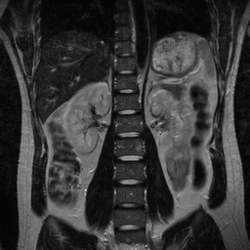

sMRI:顾名思义,是为了产生某一组织结构的一项成像技术。科学家利用了氢原子,因为人体任何组织里都有水分子(不用氧原子后面说),自然用氢原子来定位比较准确干扰少。如下图,科学家可以利用MRI探究腹腔内情况。